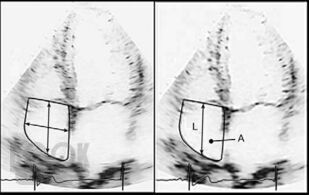

Издание содержит многочисленные рисунки и схемы, иллюстрирующие расстройства гемодинамики, методы исследования и современные оперативные вмешательства при клапанной патологии. Приведены также нормативные данные о размерах сердца и его структур, что необходимо в практической врачебной деятельности.